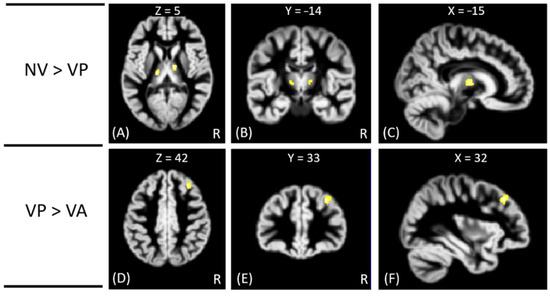

In VBM analysis, the results showed that the offenders (VA, VP, and NV) had significantly greater GM volumes than the HC group in the right superior temporal gyrus. The sub-group comparisons further revealed that only the NV group had significantly greater GM volumes than the HC group in the right superior temporal gyrus, but the VA and VP groups did not exhibit significant change in GM volume as compared to the HC group, as shown in Figure 1. In addition, the NV group had significantly greater GM volumes than the VP group in bilateral thalamus, whereas the VP group had significantly greater GM volumes than the VA group in the right middle frontal gyrus. However, no significant differences in GM volume were noted between VA and NV groups, as shown in Figure 2. The Montreal Neurological Institute (MNI) coordinates of regions with significantly different GM volumes between VA, VP, NV, and HC groups are listed in Table 2. No significant correlation was noted between GM volume and psychological scores in significant regions.

Figure 2. The VBM analysis of GM volume between the VP, VA, and NV groups. The yellow-white color indicates the significantly different GM volumes between VP and NV in the bilateral thalamus (AC), and between VA and VP in the right middle frontal gyrus (DF). The images are shown in axial (A,D), coronal (B,E), and sagittal views (C,F).

NV > VPLt. Thalamus−15−2053.82

Rt. Thalamus11−863.67

VP > VARt. Middle Frontal Gyrus3233423.98